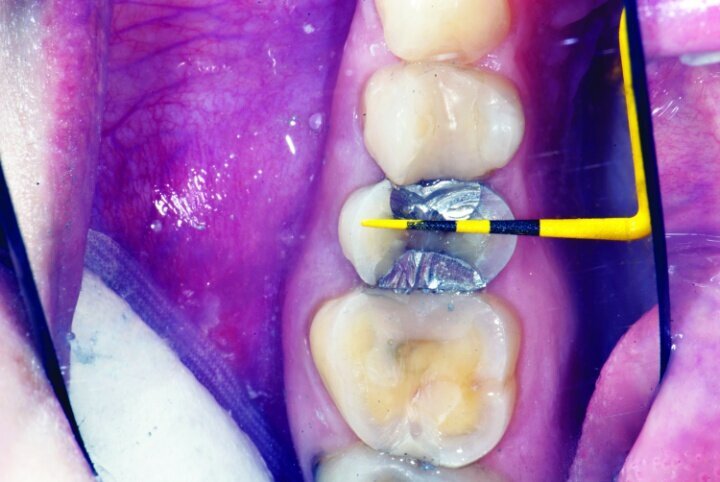

Occlusion was checked with the patient chair at a 45-degree angle. Bausch articulating paper, horseshoe shape, 200 microns thick, was used first, and the patient was instructed to chew on the paper as if chewing gum. Next, the patient was instructed to tap straight up and down on red Troll Foil articulating foil. Any marks from the chewing strokes that weren’t covered by the red paper were removed to eliminate interferences and reduce the risk of material fracture (Figs. 33a–c).

The restorations were then polished (Fig. 34). For #3 e.max restoration, the burs were NTI Cera Glaze—green, blue and yellow, in order. The green prepolisher was not used on the Empress restoration for #4.